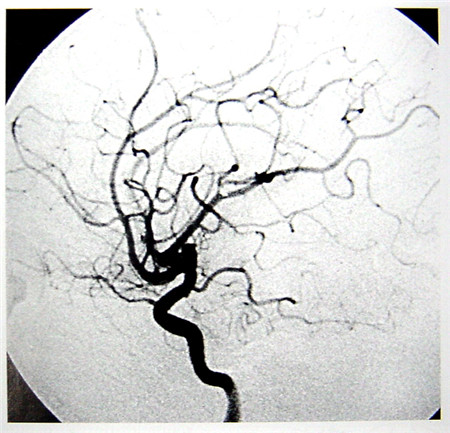

數(shù)字減影血管造影技術(shù)(Digital Subtraction Angiography,DSA)是一種新的X線成像系統(tǒng),是常規(guī)血管造影術(shù)和電子計(jì)算機(jī)圖像處理技術(shù)相結(jié)合的產(chǎn)物。DSA的成像基本原理是將受檢部位沒(méi)有注入造影劑和注入造影劑后的血管造影X線熒光圖像,分別經(jīng)影像增強(qiáng)器增益后,再用高分辨率的電視攝像管掃描,將圖像分割成許多的小方格,做成矩陣化,形成由小方格中的像素所組成的視頻圖像,經(jīng)對(duì)數(shù)增幅和模/數(shù)轉(zhuǎn)換為不同數(shù)值的數(shù)字,形成數(shù)字圖像并分別存儲(chǔ)起來(lái),然后輸入電子計(jì)算機(jī)處理并將兩幅圖像的數(shù)字信息相減,獲得的不同數(shù)值的差值信號(hào),再經(jīng)對(duì)比度增強(qiáng)和數(shù)/模轉(zhuǎn)換成普通的模擬信號(hào),獲得了去除骨骼、肌肉和其它軟組織,只留下單純血管影像的減影圖像,通過(guò)顯示器顯示出來(lái)。通過(guò)DSA處理的圖像,使血管的影像更為清晰,在進(jìn)行介入手術(shù)時(shí)更為安全。

數(shù)字減影血管造影DSA腦血管圖像顯示 核磁共振MRI掃描腦組織圖像